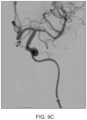

FIG.9A shows an angiogram of the previously occlusive site of the cerebral vessel ofFIG.5A after removal of the embolus;

FIG.9B is the angiogram ofFIG.9A in schematic;

FIG.9C shows an angiogram of the previously occlusive site after removal of the embolus;